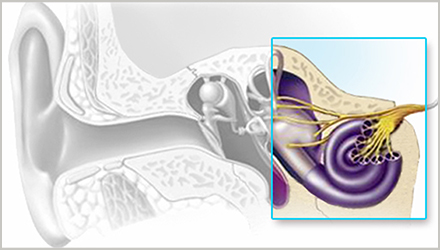

正常情况下,内耳毛细胞负责将外耳收集、中耳传导的声音转化为电脉冲,然后由听觉神经传送至大脑,再由大脑解读为可识别的声音。

感音神经性听力损失意味着,内耳毛细胞或连接内耳与大脑的神经通路受损。感音神经性听力损失是永久性的听力损失,目前我们无法通过手术来修复已受损的毛细胞,国际上通常建议使用助听器进行助听补偿。